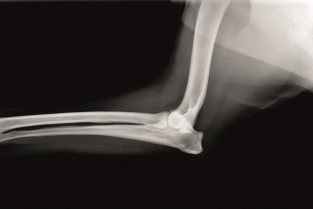

- décrire les indications et les limites des différents examens d'imagerie médicale dans la démarche diagnostic des affections du coude

L'imagerie du coude